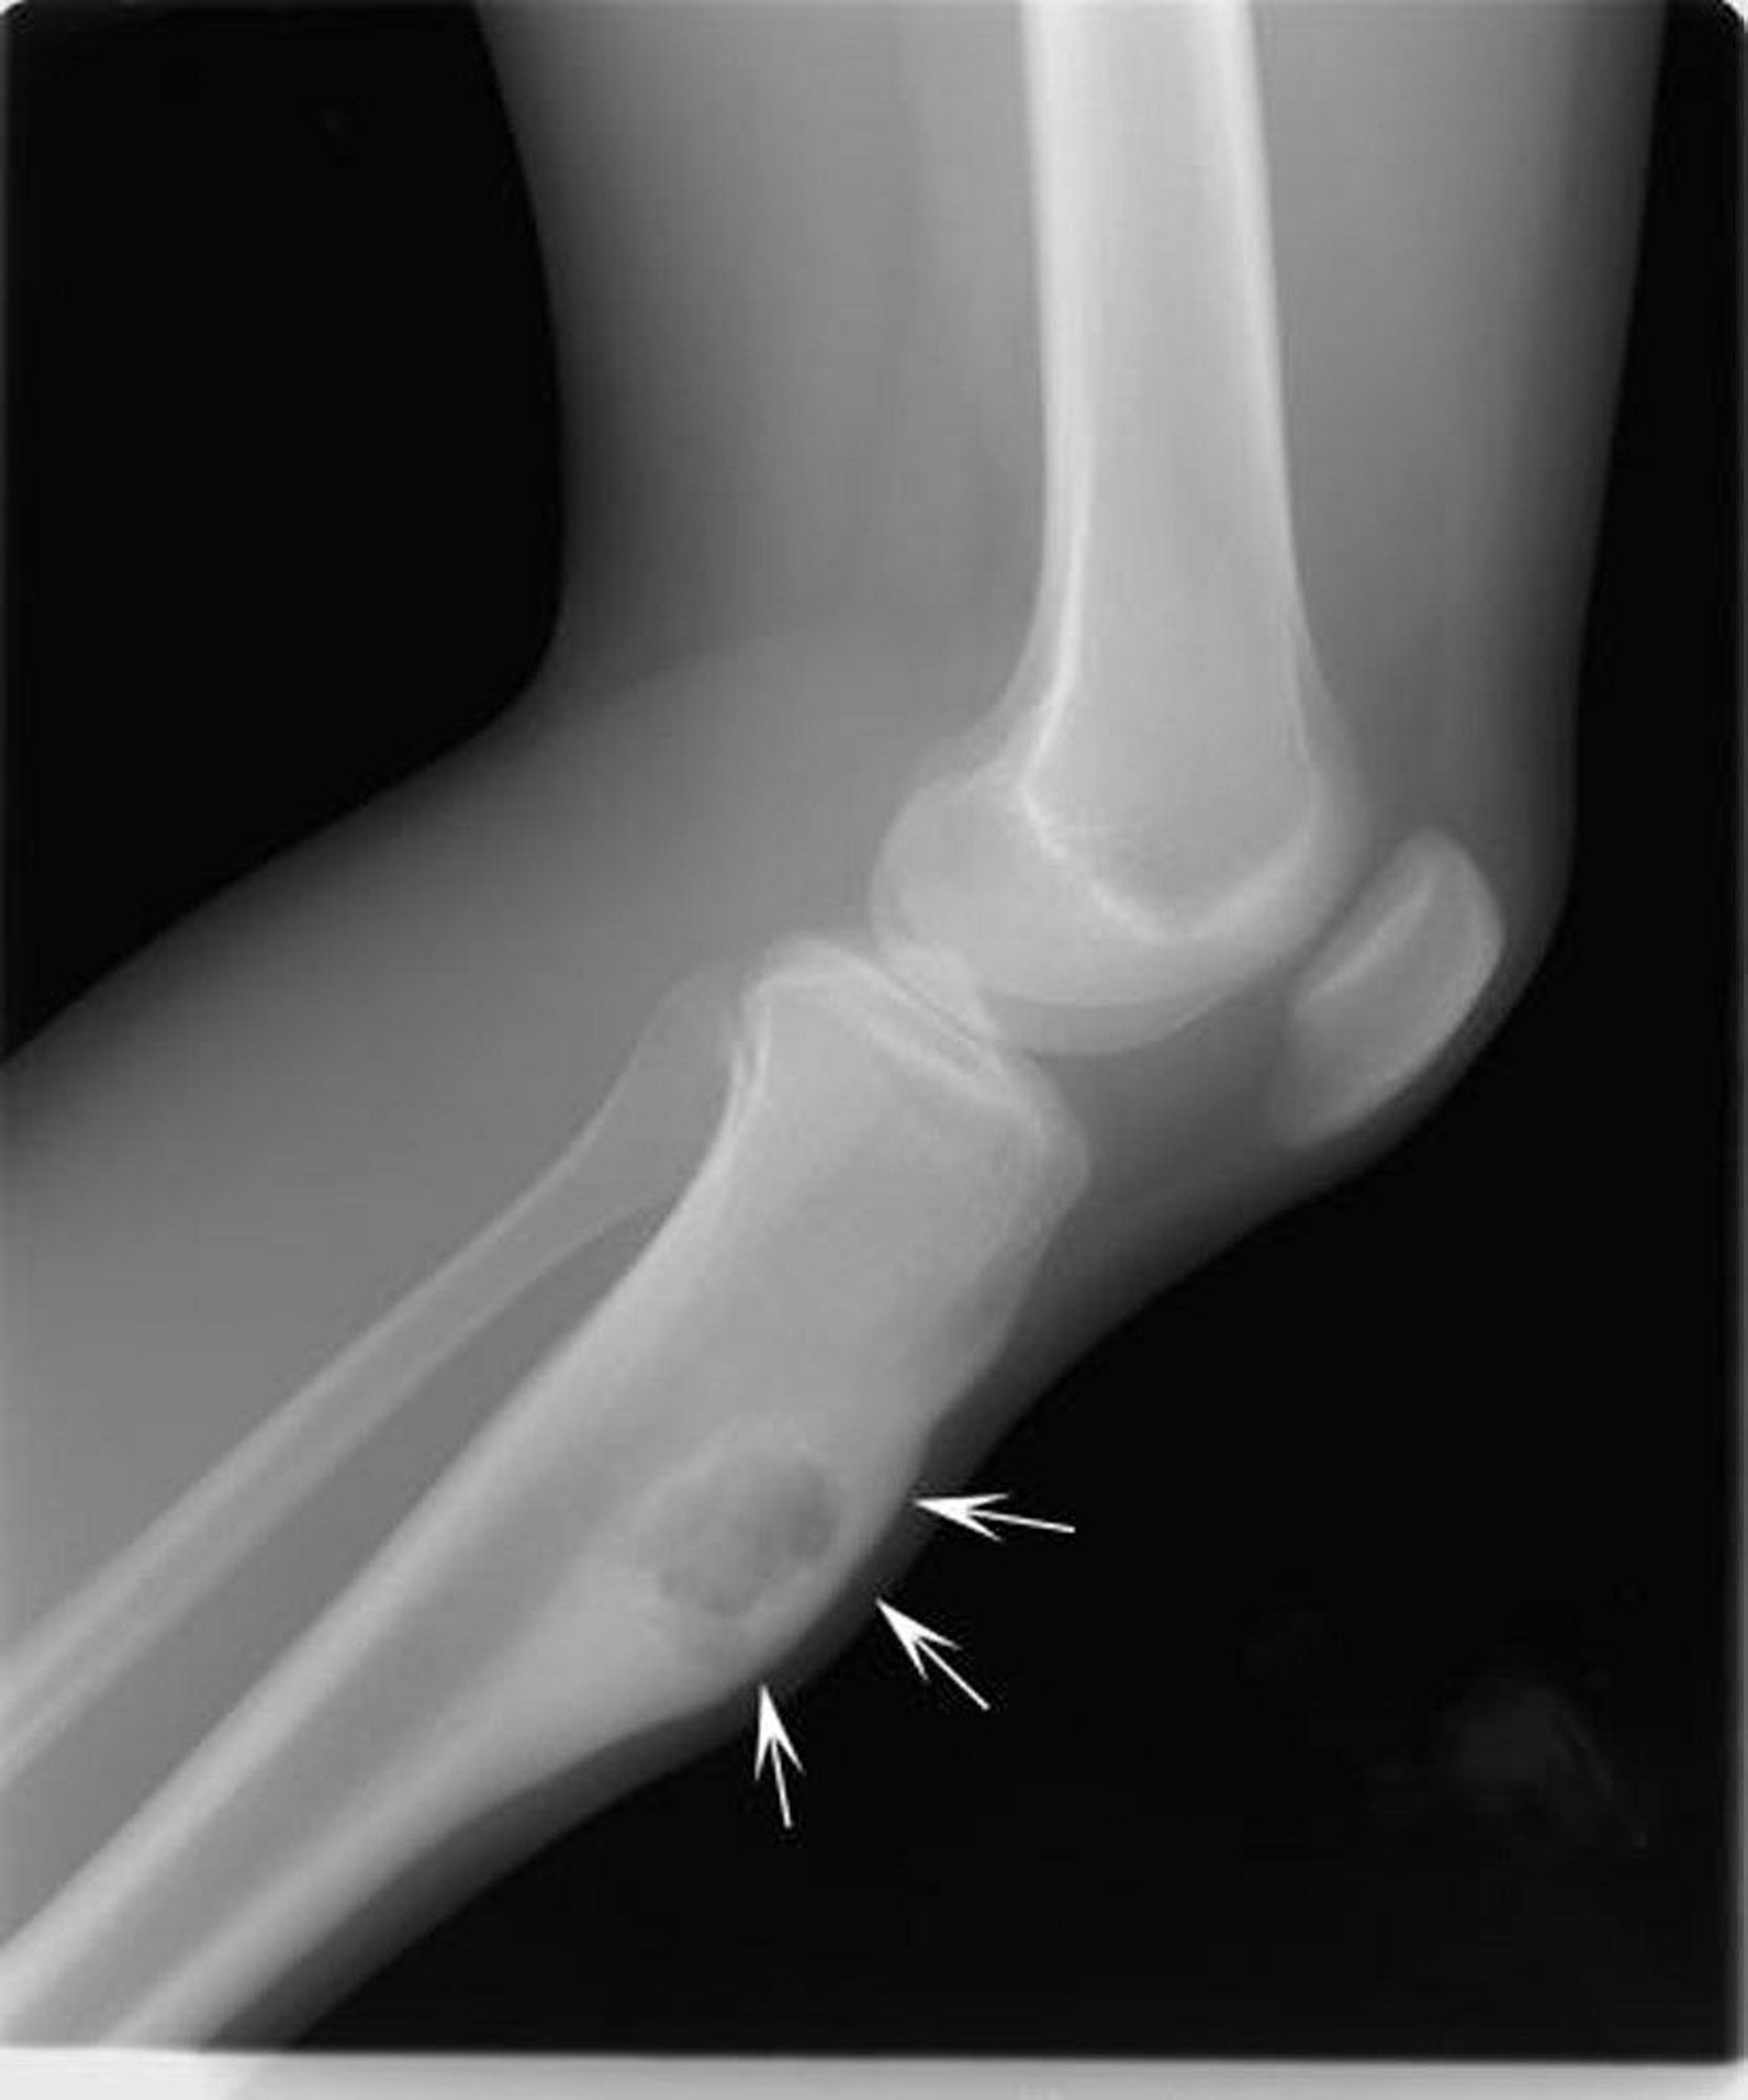

This x-ray of the knee shows a chondromyxoid fibroma (arrows) in the shin bone below the knee.

Image courtesy of Michael J. Joyce, MD, and Hakan Ilaslan, MD.